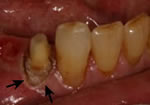

In many cases of dental decay, tooth fracture, or even in instances where an individual has "short" teeth, a crown lengthening procedure will allow us to properly construct an esthetic and functional crown, bridge, or restoration. Crown lengthening is a simple surgical procedure which adjusts the position of the gum around the affected tooth, thereby providing a more solid tooth on which to anchor the restoration of choice. A functional crown lengthening will help you regain a beautiful smile and allow you to eat and speak with comfort and confidence. A purely esthetic crown lengthening procedure to correct a "gummy" smile is often referred to as Gum Contouring.